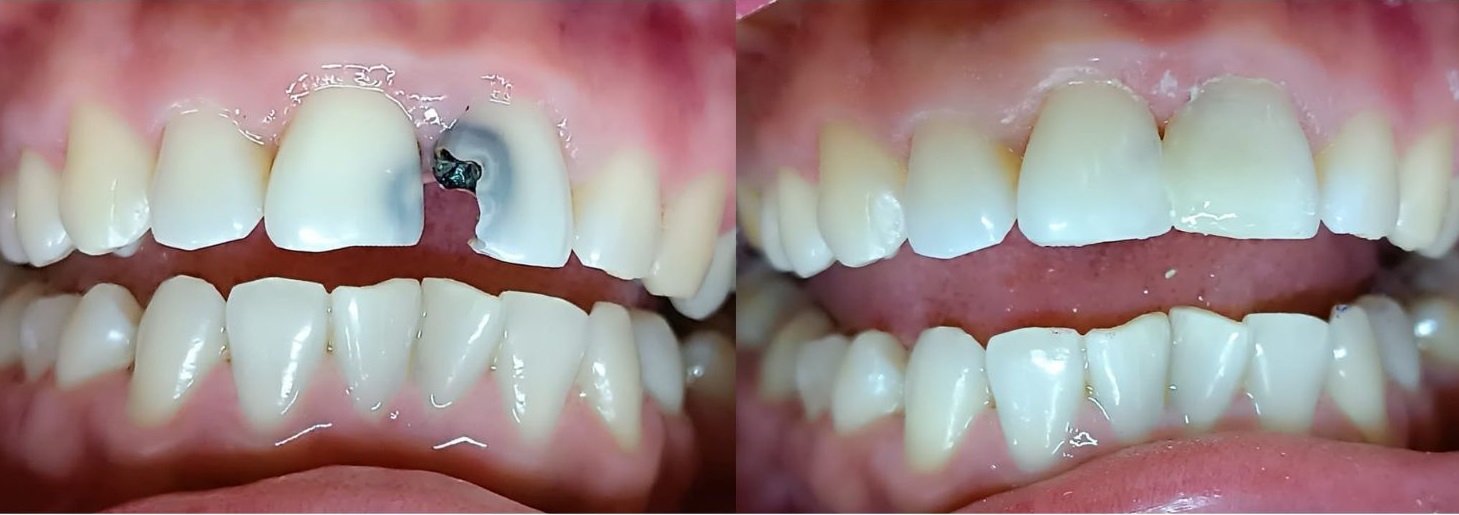

Reparamos tus piezas dentales con resinas compuestas de alta estética, devolviendo su forma, color y funcionalidad. Estos tratamientos son ideales para caries, fracturas menores o restauraciones cosméticas mínimamente invasivas.

Con nuestras carillas estéticas y coronas personalizadas podrás modificar el color, forma y tamaño de tus dientes. Estas soluciones son ideales para quienes buscan una sonrisa perfecta con resultados naturales y duraderos.